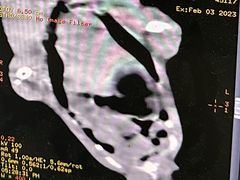

• -爱侣宠医·鹦鹉专科·小型哺乳类·异宠专科(灵石路店)

点小评6693285277 | 23-02-10

报错